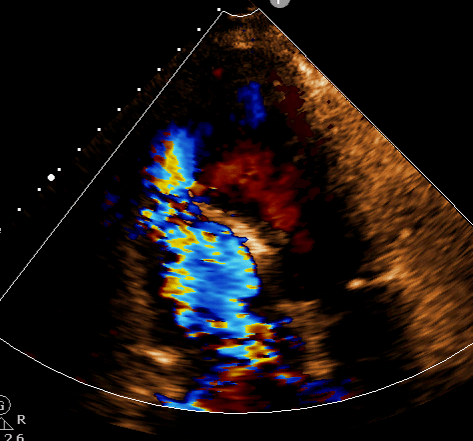

【病例分享】超声心动图诊断急性心肌梗死合并室间隔穿孔

超声心动图图片

超声心动图切面

超声心动图标准切面